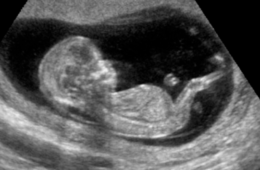

? Investigadores mexicanos descubren efectos positivos en fetos tras escuchar composiciones clásicas

Un reciente estudio realizado por investigadores en...